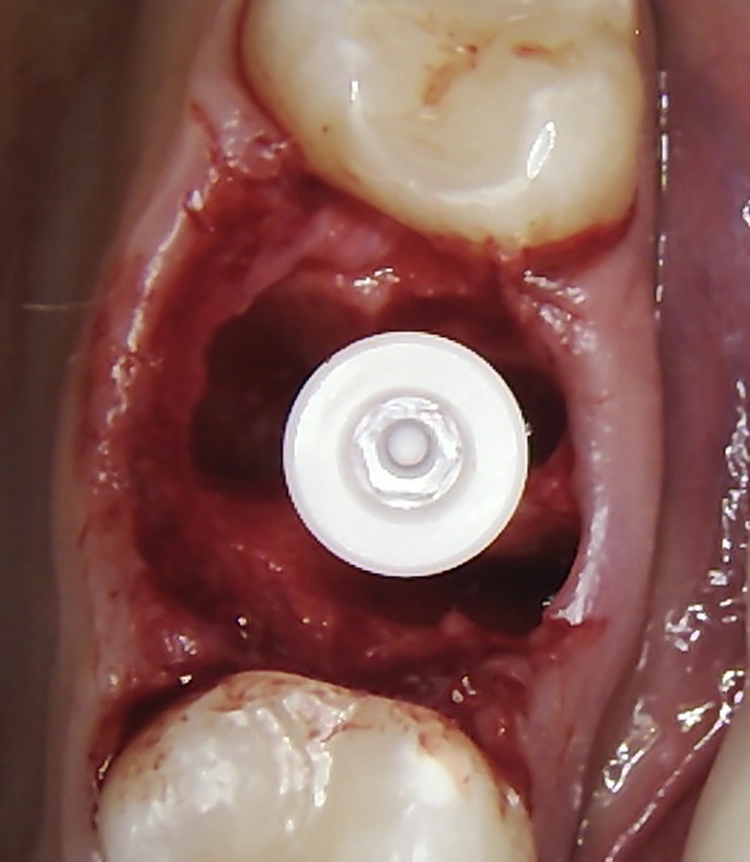

Bei dem balkonförmigen Implantat blieben die Alveolarkämme und der Kronenansatz erhalten (Abb. 4c und d). Der Spalt zwischen dem Implantat und der bukkalen Lamelle wurde mit A-PRF und einem Kollagenblock aufgefüllt, so dass keine zusätzliche Knochenaugmentation erforderlich war. Zusätzlich wurden PRF-Matrizen um, über, unter und neben dem Implantat im Knochen-Implantat-Raum positioniert (Abb. 1 bis 4b). Außerdem kam eine optionale Einheilscheibe (6 x 8 mm) zum Einsatz, um das Kollagen und die PRF zu sichern (Abb. 3b). Die Implantate zeigten bei einem Drehmoment von 35 Ncm Stabilität, welche mit dem Periotest-Gerät von Medizintechnik Gulden getestet wurde. Die Werte des Implantatstabilitätstests, die im Bereich von –8 bis 0 lagen, wurden als ideal für die Belastung angesehen (Tab. 3).

Abb. 2: Repräsentativer Fall von ABH Grad B Septus Typ II. a) Ansichten vor der Installation. Röntgenaufnahme der periapikalen Läsion an einem wurzelkanalbehandelten Molaren und klinische Ansicht der Typ-II-Socket nach der Extraktion. b) Die Ansichten nach der Installation zeigen das Implantat innerhalb des interradikulären Septums und das über dem Implantat platzierte A-PRF. c) Nachuntersuchungen nach 10 Tagen bzw. 2,1 Monaten. Die Röntgenaufnahme zeigt die Knochenbildung zwischen der Sinusmembran und dem apikalen Teil des Implantats. d) Jüngste Nachuntersuchung nach Einsetzen der Prothese.

Abb. 3: Repräsentativer Fall von Grad A Typ I. a) Präoperative Ansicht. Röntgenbild der periapikalen Läsion an einem wurzelkanalbehandelten Molaren. Die Höhe des Alveolarknochens zeigt Grad A an. b) Klinische und radiographische Ansicht der Implantatinsertion unter Verwendung einer Einheilscheibe mit großem Durchmesser (6×8 mm). A-PRF wurde um das Implantat und unter der Scheibe platziert. c) Nachuntersuchung nach 5,9 Monaten vor und nach der Zementierung und Aufbereitung. d) Jüngste Nachuntersuchung nach Einsetzen der Prothese